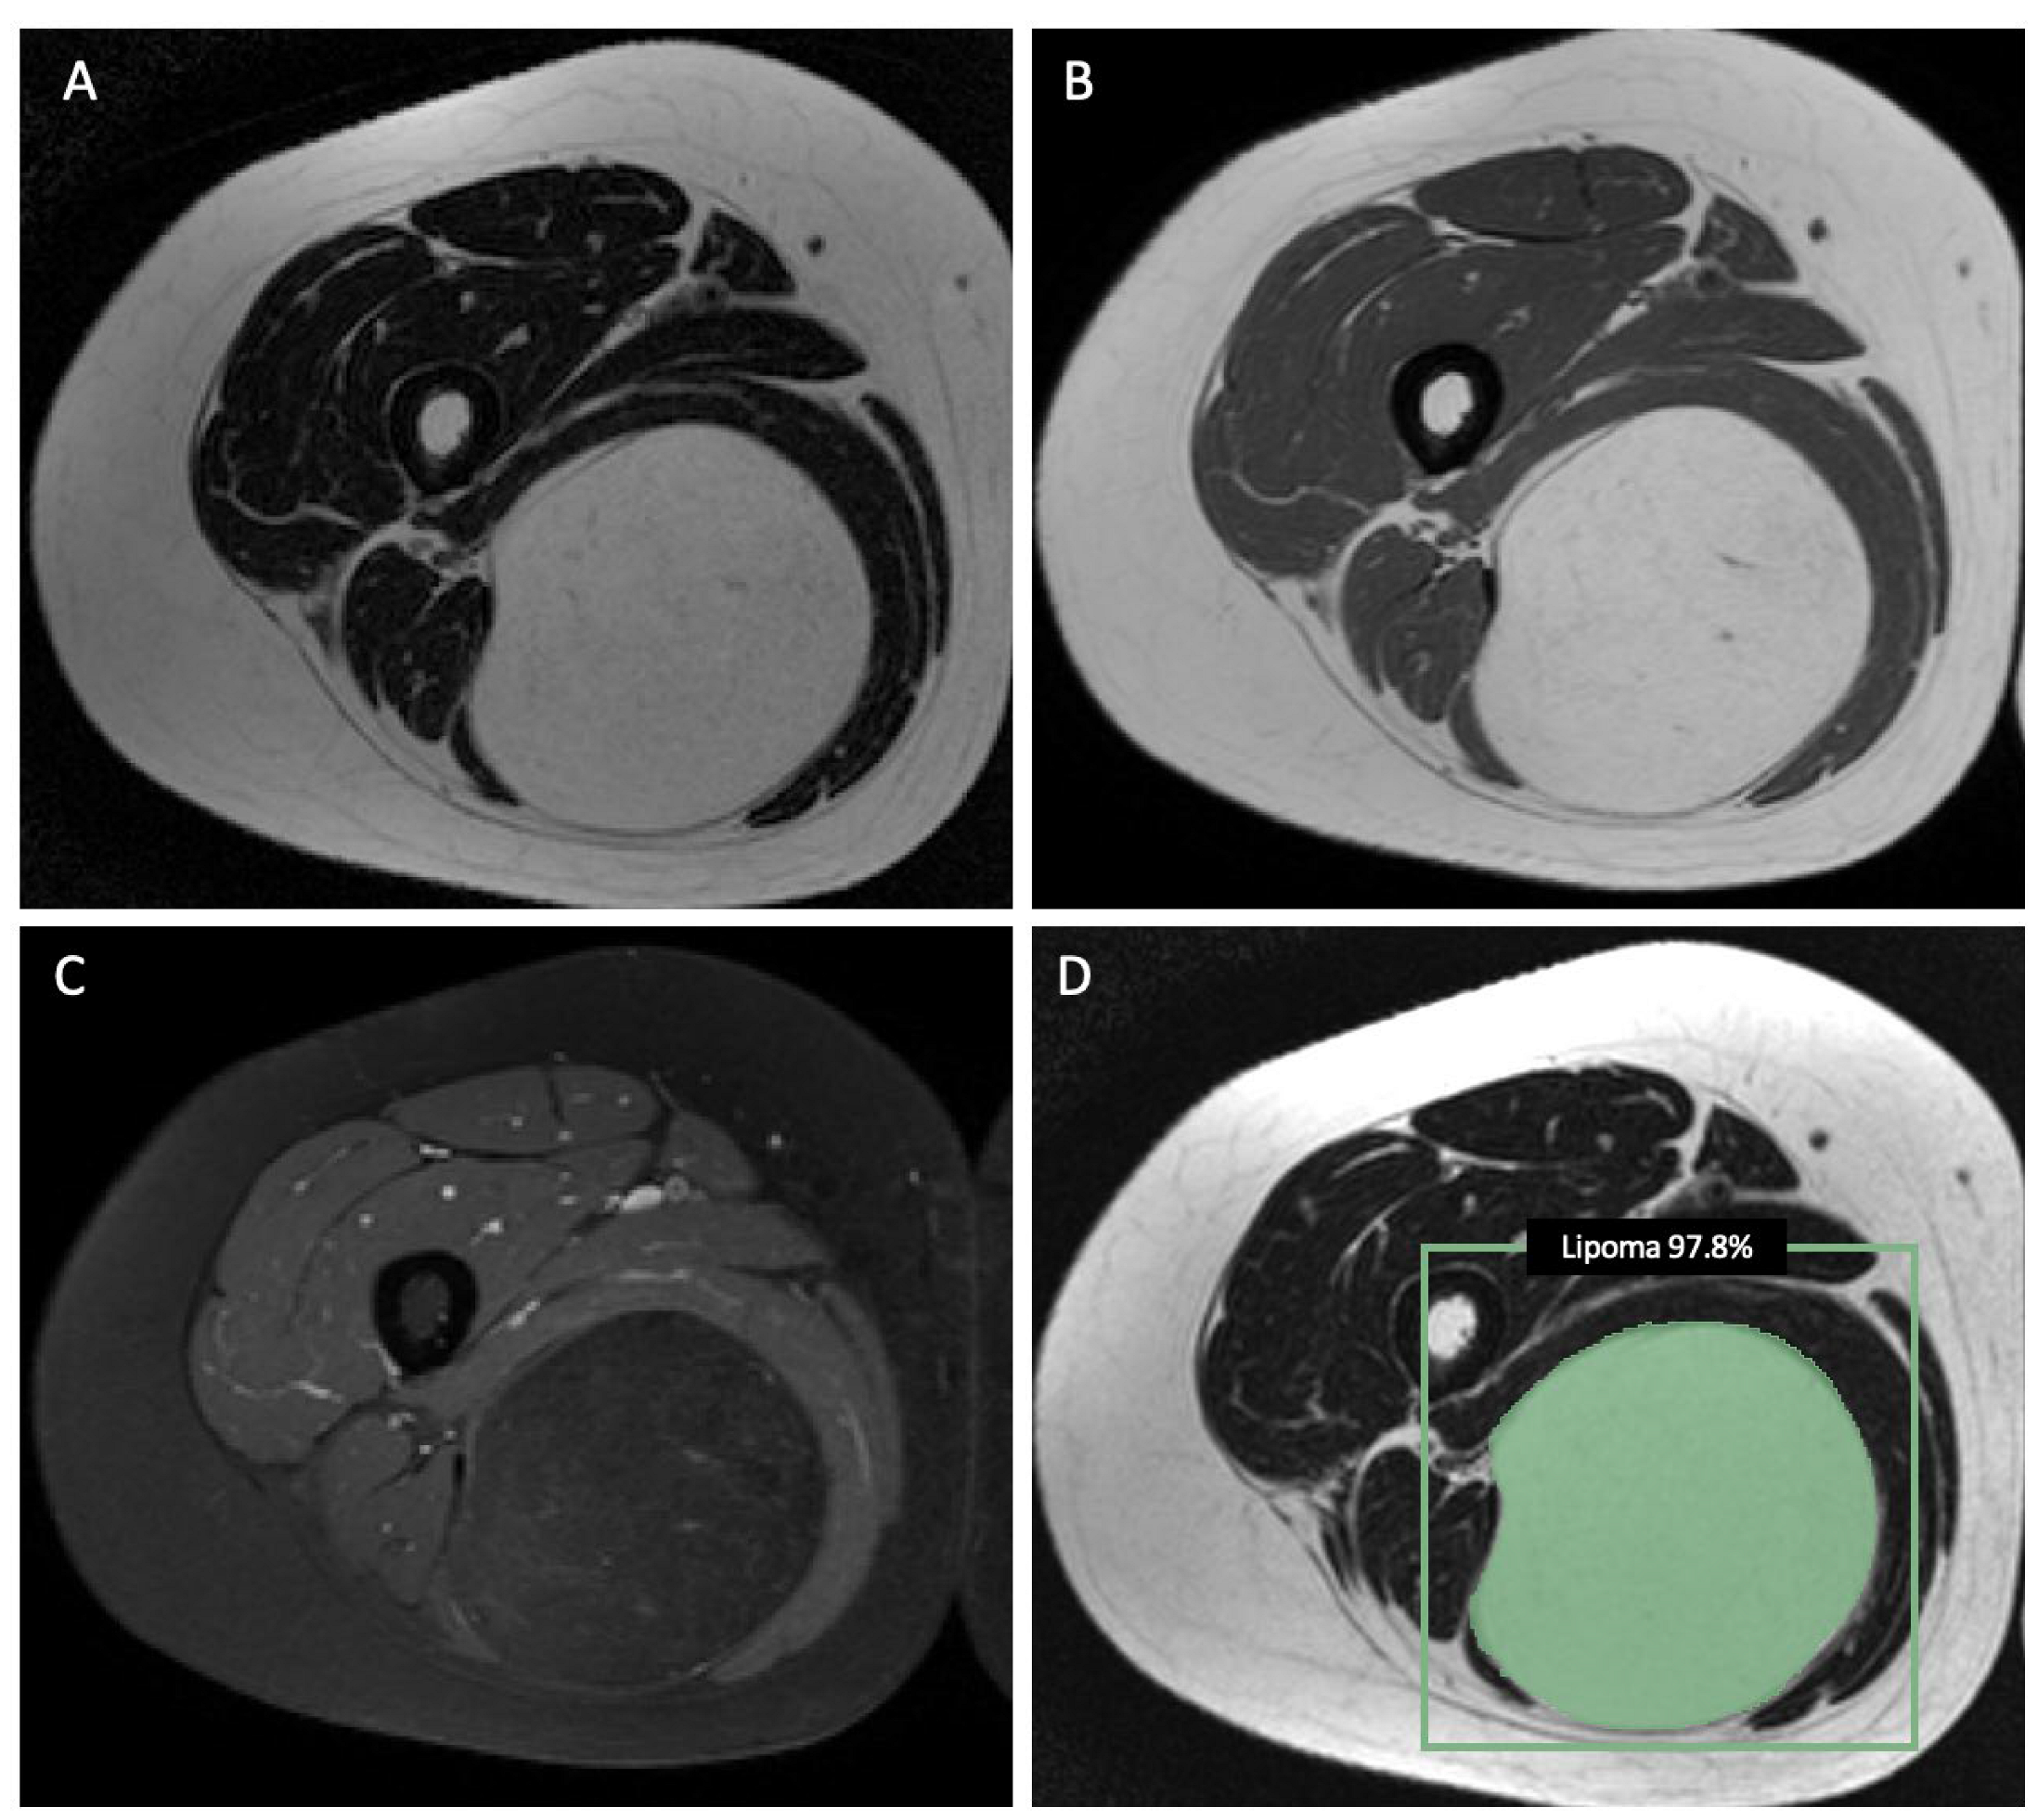

2.2. MR Imaging Protocol and Image Segmentation

2.3. Radiomic Feature Extraction and Machine-Learning Model Development